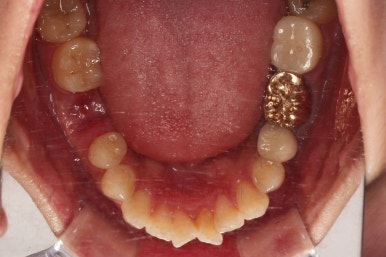

마찬가지로 초진 시 입안의 모습입니다.

입안 사진을 보니 문제점이 보이죠.

바로 어금니가 없는 상태였습니다.

장치를 부착해서 가지런하게 하고요.

발치가 필요한 치아를 하나씩 뽑아나갑니다.

어금니 발치 공간이 어마어마하게 넓죠?